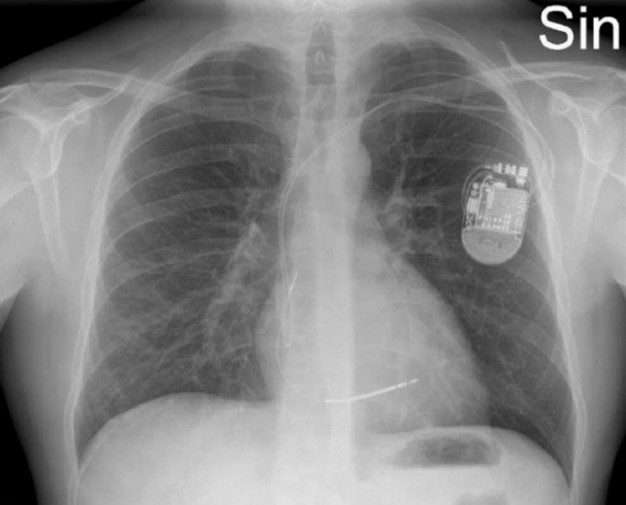

ICD (över vänster lungfält) (intern defibrillator)

Björn Lundberg, 38 år med yrsel, hjärtklappning och ibland svimning. Telemetri på avdelningen visar frekventa VES samt längre och korta VT med olika fokus. I samband med episoder av längre VT har Björn yrsel. Biokemiskt noteras mindre läckage av Troponin T utan dynamik. Akut ekokardiografi visar lätt nedsatt vänsterkammarfunktion samt hypo-/akinesi inferiort. MR visar kontrastuträde subepikardiellt i inferiora delar hjärtat.

Beslut fattas att lägga ICD pga. oro för framtida malign arytmi (VT/VF). Pat har inga klagomål utöver yrsel. Framkommer dock rethosta sedan drygt 6 månader

Patienten har flera gånger blivit uppmanad av hustrun att söka för hostan

Lungröntgen visar

Små nodulära förändringar, kring pleuran, men också runt kärl liksom mellan lober, mellan bronker – Vilka diagnoser överväger du nu? Vad blir nästa steg?